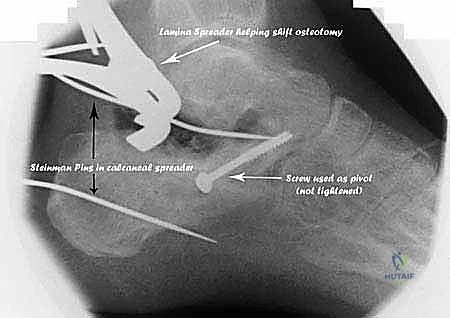

3. التصوير المقطعي المحوسب (CT Scan) مع إعادة البناء ثلاثي الأبعاد (3D Reconstruction)

لا يمكن التخطيط لجراحة تصحيح سوء التئام عظم العقب بدون أشعة مقطعية. توفر الأشعة المقطعية رؤية دقيقة للتشريح العظمي المشوه، وتحدد بدقة مكان الانحشار الشظوي، حالة الأسطح المفصلية، ومسار الأوتار. التخطيط ثلاثي الأبعاد يسمح للجراح ببناء نموذج افتراضي للقدم وتحديد أماكن القطع العظمي المطلوبة بدقة مليمترية قبل الدخول إلى غرفة العمليات.